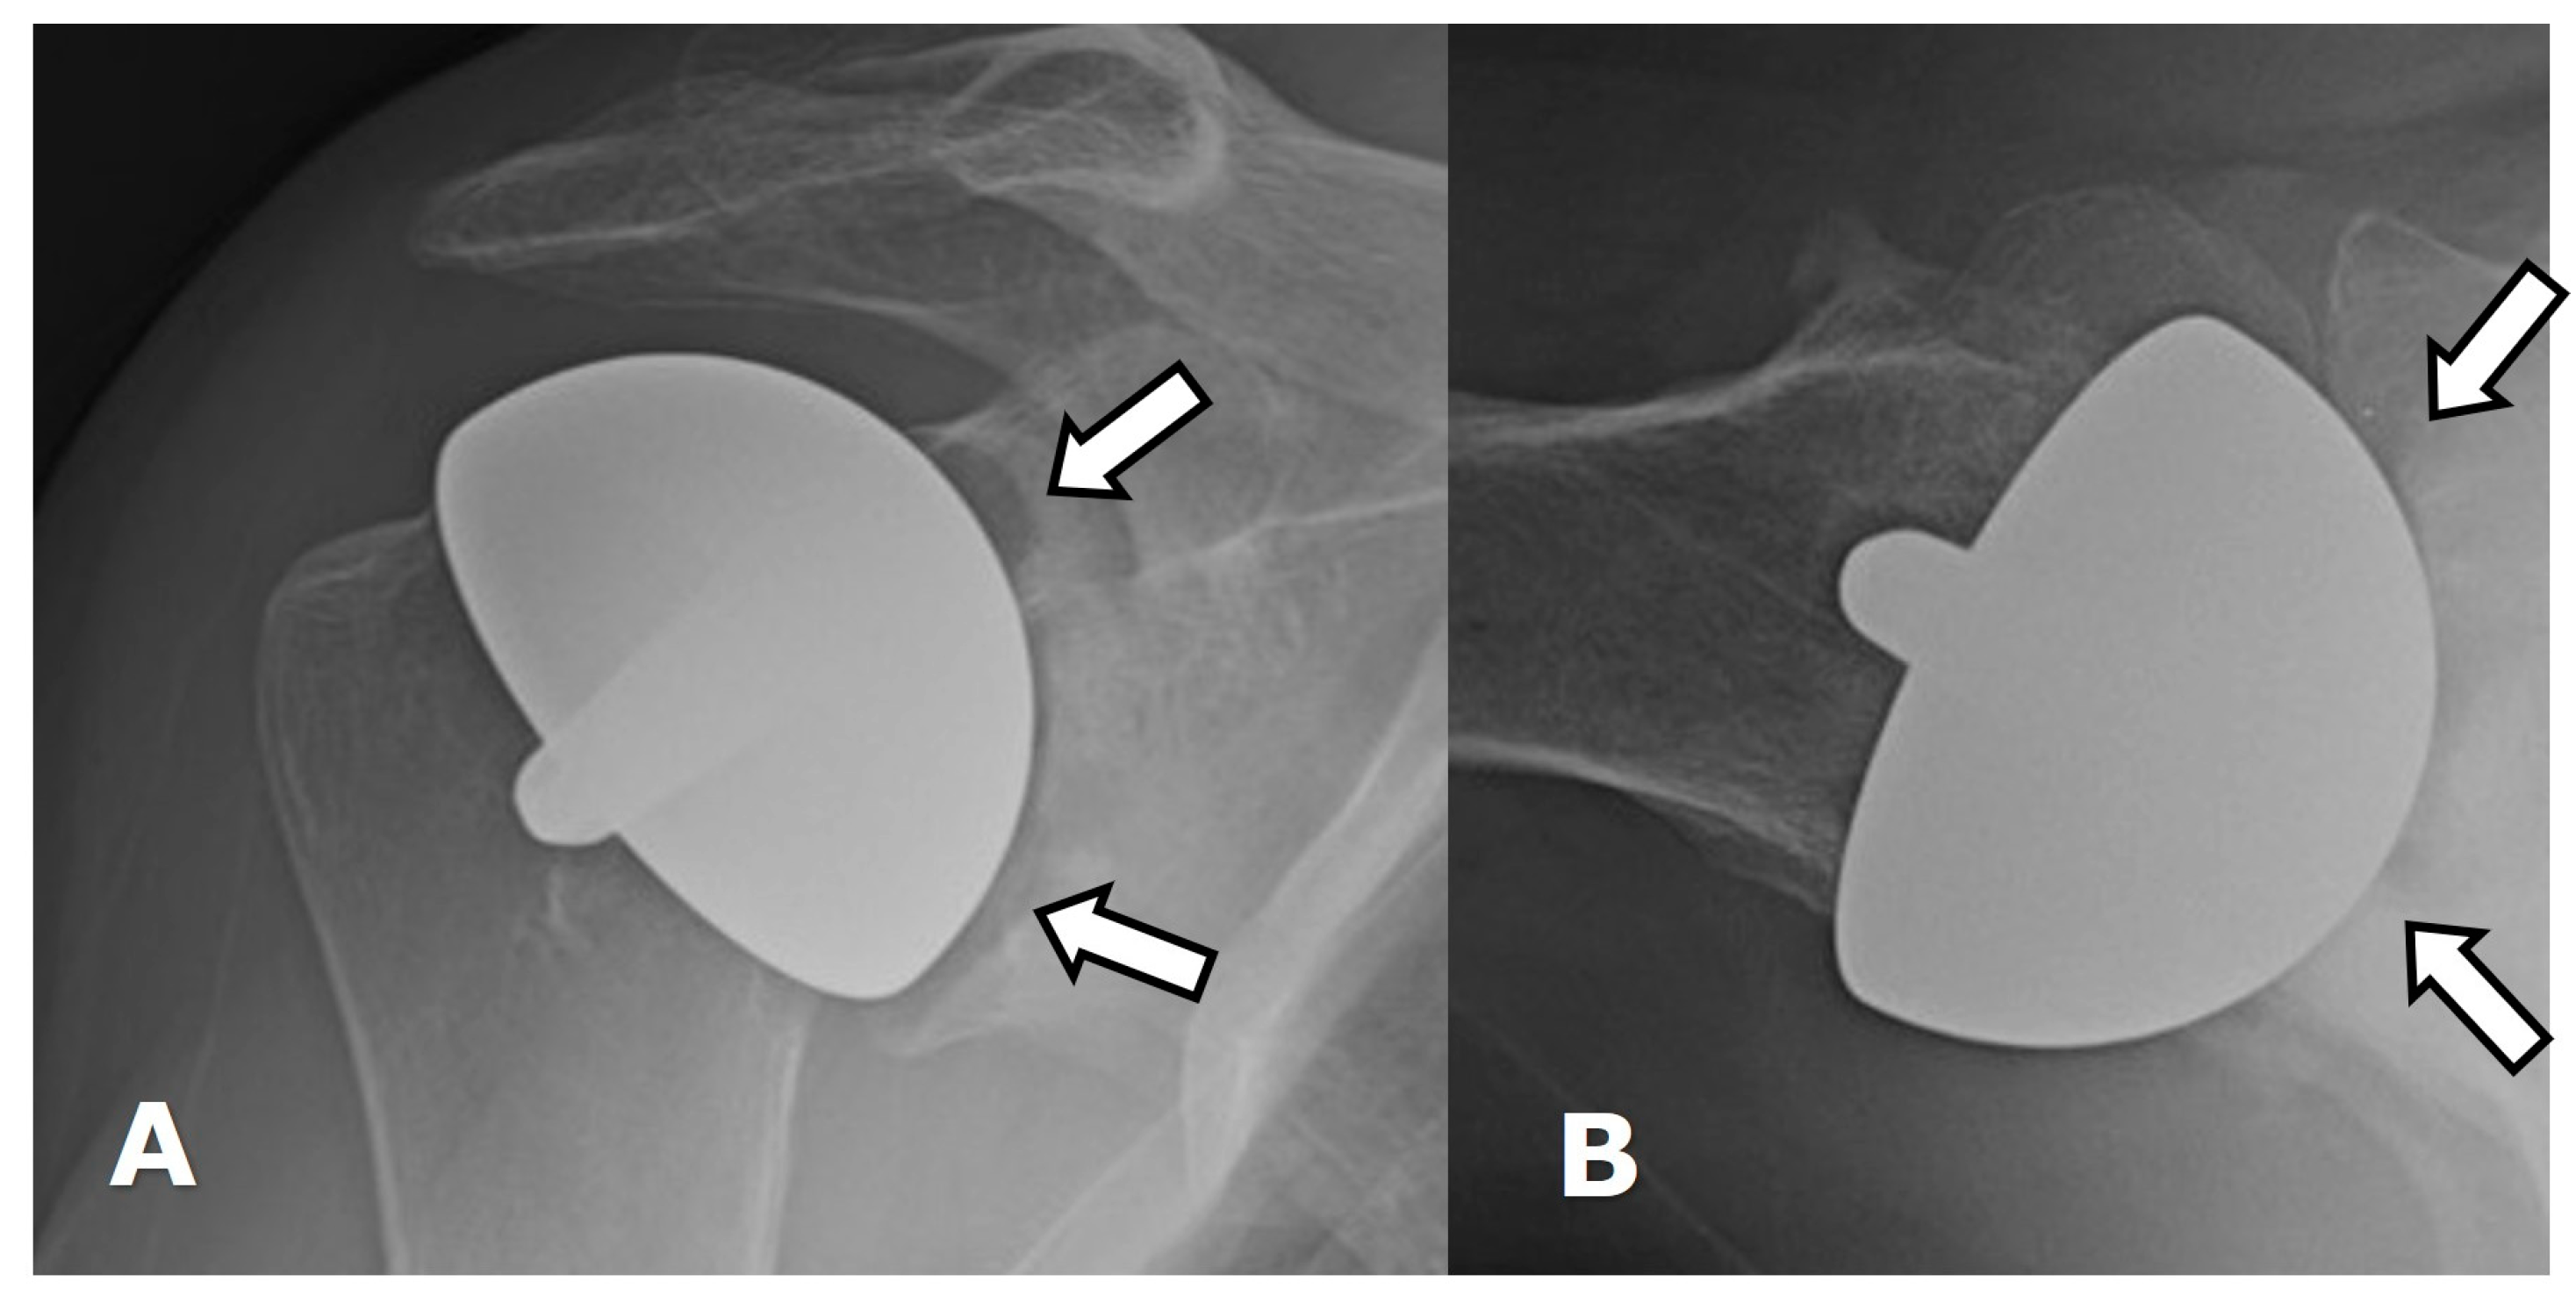

5.1.1. Humeral Head Resurfacing/Stemless Hemiarthroplasty (HHRA)